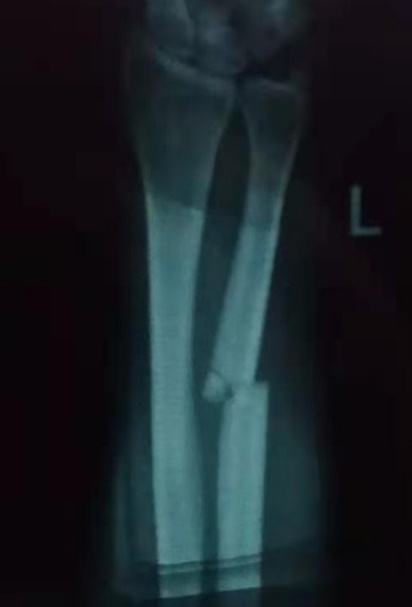

余庆芳,上海申浩律师事务所律师,“1+1”中国法律援助志愿者,服务地贵州省遵义市道真仡佬族苗族自治县。 服务期已进入倒计时,还有最后的20多天。 细数办理的79个案子,还有4个案子未结,其中庭审待判2个、待开庭2个。预计在离开前,这些案子应该能够办结。 现在,每天的工作开始有点像朝九晚五的坐班制,主要任务就是窗口接待咨询,代写法律文书,协助当事人在手机微信小程序里自行立案。工作虽然单调了些,但仍然感觉有价值、有意义。 回顾这段时间的工作,值得记录的是以下三个比较曲折的案件。 01 72岁离婚案 这可能是我经办过的涉诉离婚当事人最大年纪的案子。当事人*某,72岁,与其第二任丈夫共同生活10余年,双方虽无共同子女,但对其丈夫的一个未成年子女形成抚养关系。近年来,由于该子女将其父接走到城里居住,留下*某在乡下独自生活,*某在联系不到其丈夫的情况下,多次到村、镇甚至法院上访,成了不受待见的“上访户”。3月初的一天,*某来到法律援助窗口,说法院让她来找援助中心写离婚诉状。援助中心把代书任务交派给我。离婚诉状不到半个小时写好,让当事人交到了法院。当事人走后,我试着联系被告,建议他协商和解,这样大年纪闹离婚不太好。在弄清*某离婚诉求背后的真实原因后,在法院的主导下,两姓4个子女从外省赶回来,均愿意就赡养问题达成协议,*某遂同意撤诉。一个家庭纠纷的案件调解成功。 02 房开公司辞退保安案 4位年过五旬的农民工在一家房开公司项目工地做保安,在项目收尾阶段,劳动合同未到期,房开公司人事部主管通知他们说,工地已近尾声,不需来上班了。结果,这4个保安离职后不久,发现房开公司另聘保安顶替了他们4人的岗位。于是,被辞退的保安去找房开公司讨说法。房开公司放话说,要补偿没门,让劳动者去仲裁,“仲裁裁决一万赔一万,裁决两万赔两万”。四个保安无奈,申请了法律援助。援助中心指派我办理此案。仲裁裁决认定,房开公司违法解除合同,应分别向四名保安支付经济赔偿金7000余元,法定节假日加班工资2000余元。裁决送达后,房开公司向中级法院申请撤销仲裁。此举引发四个保安的不满,他们针对仲裁未支持的休息日加班工资1万多元和法定假日加班工资未按3倍计算(仲裁按2倍计算)提起诉讼。房开公司又以劳动者为被告,分别提起请求县法院判决“不支付经济赔偿金、法定节假日及双休日加班工资”的诉讼。 中院在收到四个保安提供的县法院立案受理通知书等相关证明文书后,裁定驳回了房开公司的撤裁申请。经过县法院4个法官4场庭审,我协助当事人与房开公司代理律师展开4场艰苦对决。5月31日,由于房开公司不接受向每人补偿6000元的调解方案,县法院作出一审判决,支持4个保安每人7000余元的经济赔偿金,3000余元的法定节假日3倍加班工资。判决比仲裁裁决金额人均多了1200元。与此同时,法院裁定驳回房开公司的起诉,理由是超过起诉期限。 此案将再经二审的可能性极大,但愿早日审结,结束这场长达一年的劳资争议,让劳动者权益维护落地实现。 03 坚持鉴定为哪般 当事人*某2019年上半年在乡村公路打工时被机器打伤左臂,医院诊断为左尺骨粉碎性骨折,钢板固定一年后二次手术将钢板取出。由于涉案工程层层转包,相关公司相互推诿,受害人找不到责任承担主体。案件指派给我以后,通过调查取证,锁定了总承包人和分包人,遂将两家公司诉至法院。为了确定是否构成伤残,征得当事人同意后,我向法院申请伤残鉴定。虽然鉴定结果并不构成伤残,拿不到残疾赔偿金,但至少可以排除不鉴定可能存在的伤残风险。 随着援助服务期终点临近,我会坚持站好最后一班岗,争取多做一些力所能及的工作,为自己的援助服务画上圆满句号而努力。